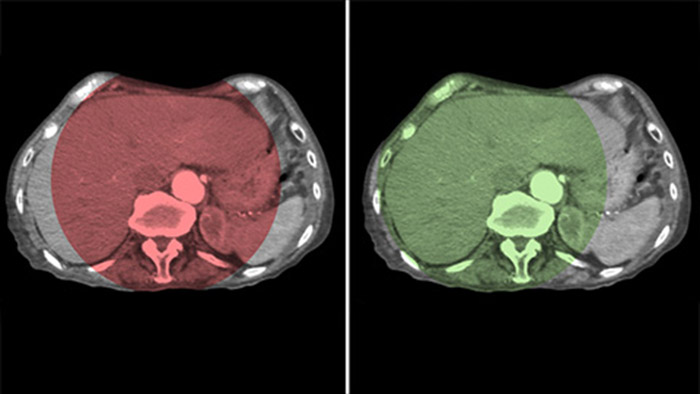

CBCT Dual enables 3D acquisition of an arterial phase to visualise vascular structures and a post-arterial (delayed phase) to visualise accumulation of contrast medium, in a single automatic step.5

Dual View allows simultaneous visualisation of two CBCT datasets. Both arterial and delayed phase can be displayed next to each other or in a single fused overlay view.